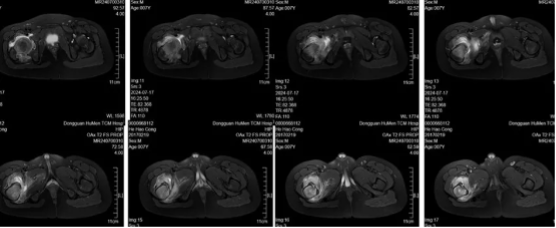

患者,男性,7岁,广东籍,因“右下肢跛行伴髋关节积液5月余”就诊,患者5月前无明显诱因开始出现右侧髋部及膝盖不适,夜间疼痛明显,逐渐加重,出现跛行。于当地医院就诊,行股骨X线、CT及MRI检查,诊断为髋关节炎,髋关节积液,当地医生无法确定,遂行全身麻醉穿刺抽液后无改善。至外省级医院就诊,考虑骨样骨瘤可能大。至我院就诊,门诊髋关节三维CT显示右侧髋部股骨颈内后方瘤巢,超过一公分。术前考虑:患者关节内骨样骨瘤,瘤巢刺激骨皮质,胫骨内侧骨皮质增厚伴瘤巢形成,疼痛较为明显,但局部骨质太硬,单纯射频消融可能无法奏效,热量无法传导,此外大量关节积液也可能导致消融范围失效;病灶较大,一次穿刺消融很难解决瘤巢,导航下实时磨除+消融可能是解决办法。遂考虑采用俯卧位下导航下行股骨颈病灶超声骨刀磨除术的策略,采用水木天蓬超声骨刀磨头头连接Suretrack连接S8导航系统,结合OsteoCoolTM射频消融。手术最大的风险在于后方穿刺需要避免损伤坐骨神经,需要轻柔操作,必要时结合B超引导鉴别,同时在使用超声骨刀的时候也需要避免神经、皮肤的热损伤。

术后第二天患者自诉原有夜间疼痛有缓解,术后一个月基本感觉不到原来的疼痛。术后复查CT可见股骨颈内明显的磨除隧道,原病灶被磨除+射频消融。术后居家休息两周后恢复正常行走,三周后上学。

图10:术前X光见右侧股骨颈内侧透亮区,边缘硬化

图11:三维CT可见明确瘤巢,髋关节大量积液

图12:髋关节核磁显示股骨近端广泛水肿,伴大量髋关节积液